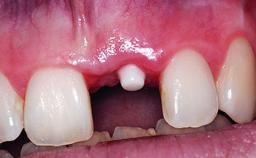

Replacement of an Upper Right Central Incisor with Root Resorption: Ridge Preservation, Delayed Placement of an NC Bone Level Roxolid Implant

A 32-year-old female Caucasian patient with a compromised maxillary right central incisor was referred to us by a general dentist. Her chief complaints were discomfort and mobility of tooth 11 with unsatisfactory esthetics due to discoloration. The patient reported a previous trauma, some years earlier, as the origin of pathology on the afflicted tooth. Anamnesis was negative for any other dental or periodontal pathology in the remaining dentition. The patient did not take any medication and reported to be a light smoker (5–10 cigs/day). She had high esthetic expectations of her treatment. The extraoral examination revealed a high smile line with full exposure of her maxillary teeth and surrounding soft tissue in the area between the second premolars.

Placement Protocol Early or late implant placement